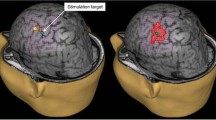

These improvements of the TMS technology in combination with standard EMG recordings have enabled accurate mapping of the motor cortex with delineation of individual muscle representations in healthy subjects (Hannula et al. 2005; Schmidt et al. 2009) and in patients with brain tumors and obscured anatomy (Krieg et al. 2012b; Picht et al. 2011a). Figure 23.1 shows a typical example of a TMS motor mapping in a case of a rolandic tumor and obscured anatomy of the central region. The 3D navigational view shows the results after TMS mapping have been performed. In the left panel of Fig. 23.1 all spots stimulated on the left hemisphere are displayed. The relevant area adjacent to the tumor has been stimulated in a dense raster. The premotor cortices have also been stimulated. In the right panel, the image displays only the spots where a muscle response was observed (MEP > 50 μV peak-to-peak amplitude). Three different hand muscles (abductor pollicis brevis, abductor digiti minimi, first dorsal interosseus) and one leg muscle (tibialis anterior) were recorded in this case. The color coding corresponds to the intensity of the response, whereby red indicates small responses (MEP 50–500 μV), yellow indicates medium responses (MEP 500–1,000 μV), and white indicates large responses (MEP > 1,000 μV). The responses close to the midline are from the leg (TA). This mapping makes it evident that the precentral gyrus has been displaced frontally.

Example of an nTMS mapping, performed on a 63 year-old female patient with a left hemisphere brain tumor, suffering from a mild hemiparesis on her right side. In the left panel, all spots stimulated on the left hemisphere are displayed. In the right panel, the image displays only the spots where a muscle response was observed (MEP > 50 μV peak-to-peak amplitude). Three different hand muscles (abductor pollicis brevis, abductor digiti minimi, first dorsal interosseus) and one leg muscle (tibialis anterior) were recorded in this case. The color coding corresponds to the intensity of the response, whereby red indicates small responses (MEP 50–500 μV), yellow indicates medium responses (MEP 500–1,000 μV), and white indicates large responses (MEP > 1,000 μV)